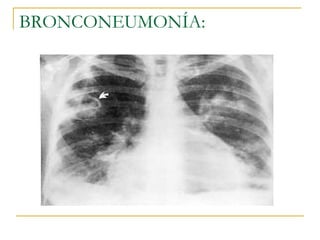

Bronconeumonía   Se produce una intensa inflamación en las vías aéreas y el parénquima pulmonar contiguo Opacidades en parches de contornos poco definidos que ocupan mas de un lóbulo   todo un pulmón o de forma bilateral   Puede estar presente el broncograma aéreo   Puede originarse con diversos organismos, aunque el más habitual son las bacterias. Es fácil que se origine después de haber sufrido un resfriado

Grupos que mas afecta:  los niños, los ancianos  , pacientes crónicos de diversas enfermedades como el asma, la diabetes o las cardiopatías  Bronconeumonía  curso mas agresivo que neumonia lobar Los sitios primarios de lesión son los bronquíolos terminales y respiratorios  con formación de úlceras e infiltración de sus paredes por   leucocitos   polimorfonucleares

engrosamiento peribronquial y tapones de moco  En contraste con la neumonía  lobar  que se caracteriza  por  atelectasia infrecuente, la bronconeumonía es una causa común de atelectasia  la  se ha denominado neumonía atelectásica .

Radiografía de torax, que muestra bronconeumonía en el pulmón derecho.